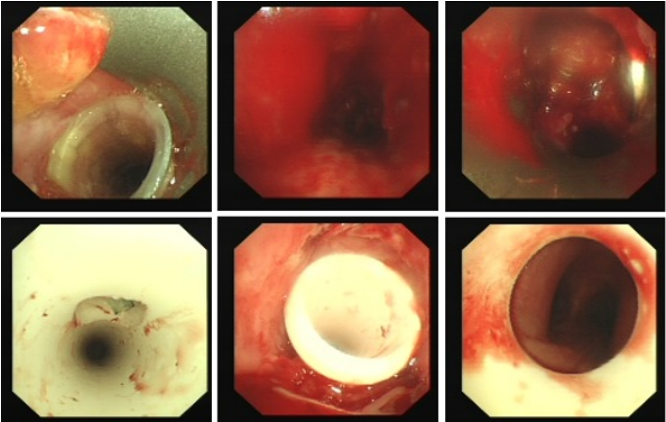

12月8日复查胸部CT,气管管径较前明显增宽(图10)。患者于12月14日出院,于当地定期复查。病例3:80岁,男性,发现颈部肿块5年,咳嗽气促1个月入院(2024年1月6日)。2019年1月14日曾于外院置入气管硅酮支架。术前(1月6日):HR 95次/min,R 22次/min,静息下SpO2 97%(FiO2 29%),活动后喘鸣。1月8日硬镜示:气管上段膜部肉芽样新生物致管腔混合性重度狭窄(外压为主),冷冻+直钳清除气管上段膜部新生物(质韧,活检困难),术后直钳上调硅酮支架至气管起始部,完全覆盖狭窄处(图11),术后气促明显改善。术后病理:鳞状上皮化生,伴轻度非典型增生。1月12日凌晨1:09突发气促加重,喘鸣明显,HR 140次/min,BP 200/102 mmHg,R 35次/min,SpO2 97%(FiO2 35%)。紧急联系介入和麻醉团队进行急诊介入治疗,无痛喉罩下正压通气,患者喘鸣消失。支气管镜示:声门下腔水肿,气管起始部见大块坏死物堵塞管腔,随呼吸呈活瓣样,管腔明显狭窄,予冷冻+钳夹清理,支架未移位(图12)。

1月12日复查CT:支架位置良好(图13)。予无创通气与高流量交替,拟T管置入。1月14日患者夜间出现刺激性咳嗽,1月15日复查气管镜(软镜)示:声门下腔水肿并坏死物致管腔中度狭窄(图14),冷冻清理坏死物后见硅酮支架下移10 mm,支架第二次移位;声门及声门下腔注入地塞米松5 mg。硅酮支架难题就是肉芽增生和移位,与家属充分沟通后同意T管置入。1月17日全麻硬镜:声门下腔及气管起始部黏膜水肿并坏死物致管腔轻度狭窄,取出硅酮支架,置入T管(图15)。1月19日和20日两次复查气管镜:T管在位,管腔上缘少许坏死物(图16)。病例4:85岁,女性,反复气促2年,外院住院考虑气管外压性狭窄,支架置入失败,心跳骤停,困难插管后3月7日转入我科。入科:气管插管,HR 96次/min,BP 107/86 mmHg,R 24次/min,SpO2 98%(FiO2 100%)。腹膨隆明显。急查胸腹CT示腹腔、纵隔、胸壁及颈部多发积气(图17)。予腹腔穿刺排气。3月11日复查CT示积气明显减少(图18)。3月12日行全院大会诊,考虑结节性甲状腺肿可能,可考虑外科手术。下一步治疗面临难题:继续插管?还是支架置入后手术?与家属充分沟通后,家属拒绝再次支架置入,故继续插管并于3月15日于耳鼻喉科行甲状腺全切术+气管悬吊重建术。术后第3天(3月18日)拔除气管导管,3月28日顺利出院(图19)。因此,并非所有良性气道狭窄都需要介入治疗,解除原发病因最重要。